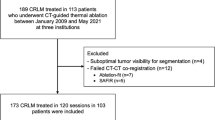

After applying the exclusion criteria described above, 108 out of 174 (62%) CRLMs were eligible for 3D assessment evaluation (Fig. 2). In 15 of these eligible cases (13.8%), rigid registration did not ensure optimal image alignment. Complete 3D assessment was performed in 93 CRLMs in a total of 72 patients (Table 1). An example of visualization of the results of 3D assessment is shown in Fig. 3. The average time to perform 3D volumetric margin analysis was 4.26 ± 1.5 min for each ablation site.